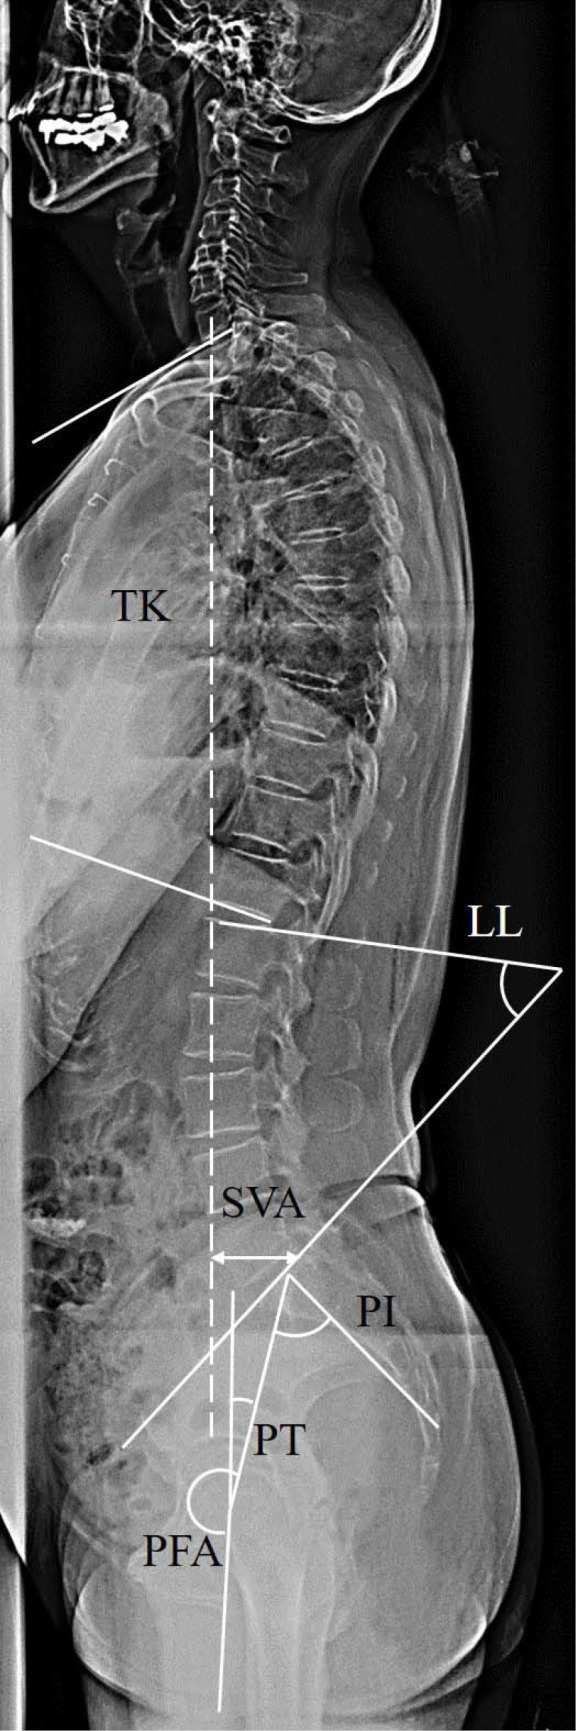

Methods: This study was a retrospective cross-sectional study. We included 398 consecutive female patients treated for osteoporosis at our outpatient department between November 2017 and June 2022. Patients with any of the following were excluded from the study: (I) those whose plain whole-spine radiographs did not cover the femurs, (II) those with fractures in the vertebrae or lower extremities, (III) those with a history of surgery of the spine or of the lower extremities, (IV) those with scoliosis with a Cobb angle ≥10° in the anteroposterior radiograph, and (V) those with transitional vertebrae. Sixty-two patients were divided into normal and malalignment groups based on their sagittal spinal alignment. The patients underwent plain whole-spine radiography as a routine examination. A linear approximation between the pelvic femoral angle (PFA), representing hip extension, and PI-LL was obtained in both groups. The optimal PFA of each patient was obtained by substituting the PI-LL into the linear approximation of the normal group. The difference between the optimal and measured PFA was defined as the ΔPFA for each patient. The correlation between the ΔPFA and sagittal vertical axis (SVA) was evaluated in both groups.

Results: The PFA and PI-LL were correlated in both groups. The malalignment group had a significantly greater ΔPFA than the normal group. ΔPFA was correlated with SVA only in the malalignment group.

Conclusions: The magnitude of the ΔPFA indicated insufficient hip extension to compensate for the spinopelvic mismatch during upright standing.